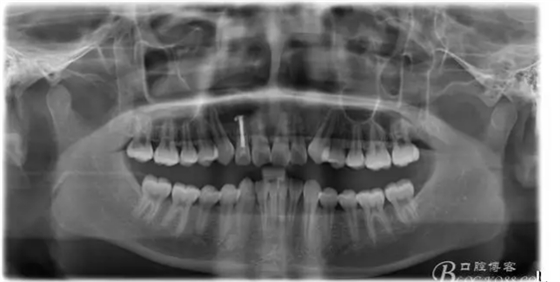

1.術前的根尖片檢查及根管治療影像:

圖17. 術后的全景片影像: